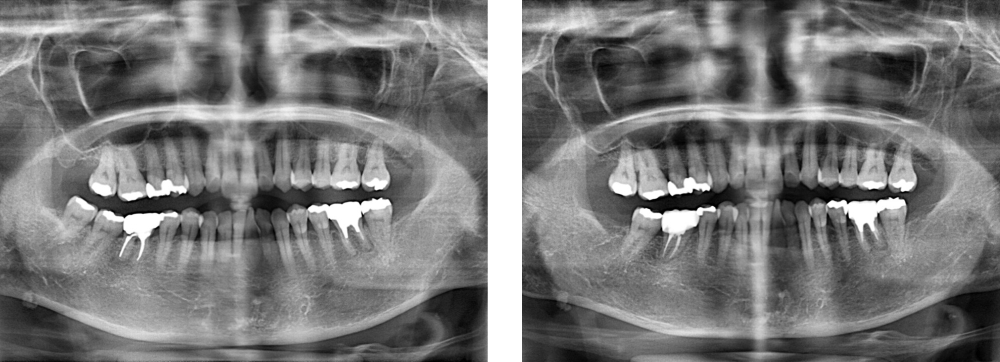

口腔外科

術前

術後

| 治療内容 | 歯根破折のため保存不可能 移植して根管治療を行い、補綴処置を行った ※術後のレントゲンは2年後のレントゲンです |

|---|---|

| 治療期間・回数 | 5カ月・11回 |

| 費用 | 保険適用となります |

| リスク・副作用 |

|